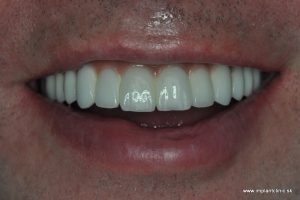

Ponúkame vám prípad pacienta, ktorý potreboval celkovú rekonštrukciu chrupu pomocou zubných implantátov a zubných koruniek.

Na základe RTG a CT vyšetrenia náš hlavný implantológ MUDr. Marek Salka, odporučil pacientovi extrakcie nevyhovujúceho chrupu a následne celkovú rekonštrukciu hornej a dolnej čeľuste pomocou zubných implantátov s fixným keramickým oblúkom do vrchnej čeľuste a náhrada stoličiek v dolnom chrupe pomocou zubných implantátov a estetická úprava ostatných zubov pomocou zubných koruniek.

Plán ošetrenia pacienta Jakuba, a teda celková rekonštrukcia jeho chrupu, zahŕňal implantáciu 7 zubných implantátov do hornej čeľuste a 3 zubné implantáty do sánky. V spodnej čeľusti mal pacient na pláne ošetrenia naplánovaných ešte 10 zubných koruniek.

Nasledovala ešte kontrola záhryzu niekoľko dní po zákroku a o dva mesiace po implantácii nás pacient navštívil pre kontrolu a odobratie odtlačkov pre výrobu finálnych implantátových koruniek, ktoré sme nasadili pri pacientovej následnej návšteve u nás na klinike.